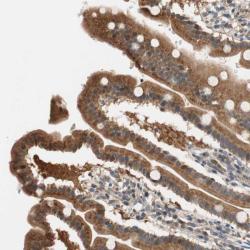

Supportive validation

- Experimental details

- Immunohistochemical staining of human duodenum shows distinct cytoplasmic positivity in glandular cells.

- Validation comment

- Staining pattern partly consistent with experimental and/or bioinformatic data.